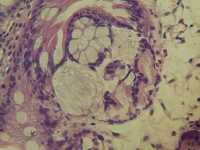

慢性炎有肠化

图1有粘液样变,有问题吗?同人们有什么看法?谢谢

(吻合口)慢性轻度萎缩性胃炎伴肠化,粘膜水肿及糜烂。